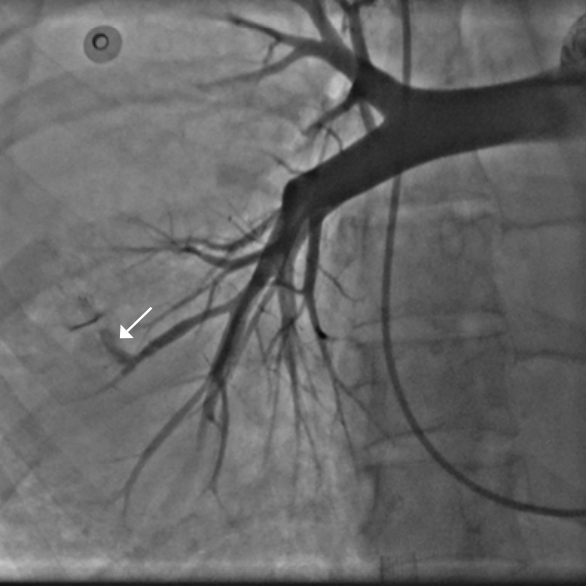

пЧКВ в интервале 12-48 ч от начала ИМпST у малосимптомных/бессимптомных пациентов

В исследовании BRAVE-2 Schömig A, et al., 2005 [30] включали больных ИМпST с госпитализацией в течение 12-48 ч от начала симптомов, у которых не было симптомов заболевания (боль, СН, аритмия). Пациенты рандомизировались в две группы. В первой выполнялась стратегия пЧКВ (n=182), во второй проводилось консервативное лечение (n=183). Первичными конечными точками были: 1) суррогатная — объем некроза миокарда на основании однофотонной эмиссионной компьютерной томографии; 2) твердая — комбинированная клиническая конечная точка в течение 30 дней (смерть, рецидив ИМ, инсульт). В результате размер некроза миокарда был достоверно меньше в группе пЧКВ (8% vs 13%, Р=0,001), а по комбинированной твердой конечной точке к 30 дню наблюдения различий между группами не было найдено, хотя в абсолютных величинах число неблагоприятных исходов в группе ЧКВ было меньшим (4,4% vs 6,6%, Р=0,37). Авторы сделали заключение о уменьшении размера некроза при стратегии пЧКВ и поздних сроках стентирования (12-48 ч от момента заболевания ИМпST) у бессимптомных пациентов. Продолжая исследование BRAVE-2, Ndrepepa G, et al., 2009 [31] продемонстрировали, что к 4 году наблюдения группа со стратегией пЧКВ имела меньшее число смертельных исходов (11,1% vs 18,9% в группе консервативного лечения, Р=0,047).

Исследование, основанное на анализе ретроспективных данных, полученных из французского регистра FAST-MI, продемонстрировало достоверно лучшие результаты стратегии пЧКВ, чем консервативного лечения для пациентов ИМпST, поступивших через 12-48 ч после начала заболевания. В группе пЧКВ зарегистрировано достоверно меньшее число случаев смерти от всех причин, как в ближайшие (к 30 сут. наблюдения 2,1% в группе пЧКВ vs 7,2% в группе консервативной терапии, Р<0,001), так и в отдаленные сроки лечения (к 58 мес. наблюдения 30,4% vs 78,7%, соответственно, Р<0,001) [32].

У бессимптомных больных, к сожалению, интервал времени >12 ч от начала ИМпST не является критерием окончательно полного некроза миокарда, и дополнительное спасение миокарда происходит и при пЧКВ за пределами 12 ч (например, в промежуток 12-72 ч) даже у больных с окклюзированной ИСА [33]. Хотя мы имеем европейские рекомендации о необходимости рутинного рассмотрения целесообразности пЧКВ у пациентов, госпитализированных через 12-48 ч от начала ИМпST, четких критериев отбора на механическую реваскуляризацию в этой группе больных нет. С учетом этого, и принимая во внимание доказанный риск развития синдрома невосстановленного коронарного кровотока (no-reflow) в группе позднего поступления больных ИМпST с окклюзированной ИСА [34], протоколы ведения больных ИМпST должны предусматривать рутинное стентирование ИСА у бессимптомных больных при госпитализации после 12 ч только в случае стенозированной (но не окклюзированной) ИСА.